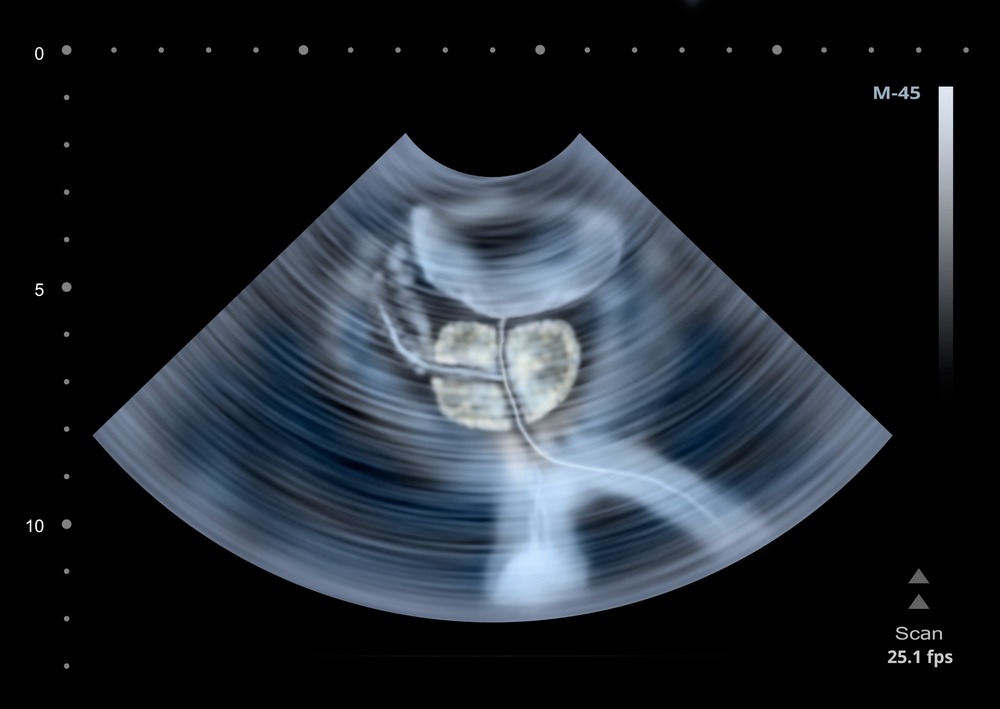

A transrectal prostate ultrasound uses a small probe (camera) that is inserted into the rectum for having a closer look at the prostate for medical imaging to check the prostate inside your lower abdominal cavity. This includes bladder with the measurement of bladder volume before and after emptying, prostate, and seminal vesicles.

Prostate ultrasound is a non-invasive (except transrectal scan for the prostate in which a small probe (camera) is inserted into the rectum for having a closer look at the prostate) medical imaging to check the prostate inside your lower abdominal cavity. This includes bladder with the measurement of bladder volume before and after emptying, prostate, and seminal vesicles.